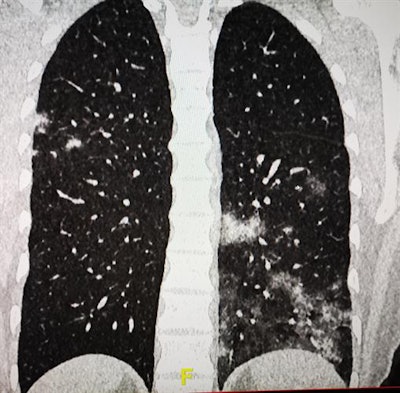

Thanks to the national and international publications and information campaigns, we have become quite aware of the COVID-19 CT features, but soon we had quite a lot of nontypical cases, including patients with extrathoracic findings or severe cases in young people. We have also had some patients from our hemodialysis center presenting with less severe cases and many patients with ear, nose, and throat symptoms or associated diseases, including pulmonary emboli. This is quite a problem in COVID-19 cases that require cooperation with clinicians, especially emergency specialists.